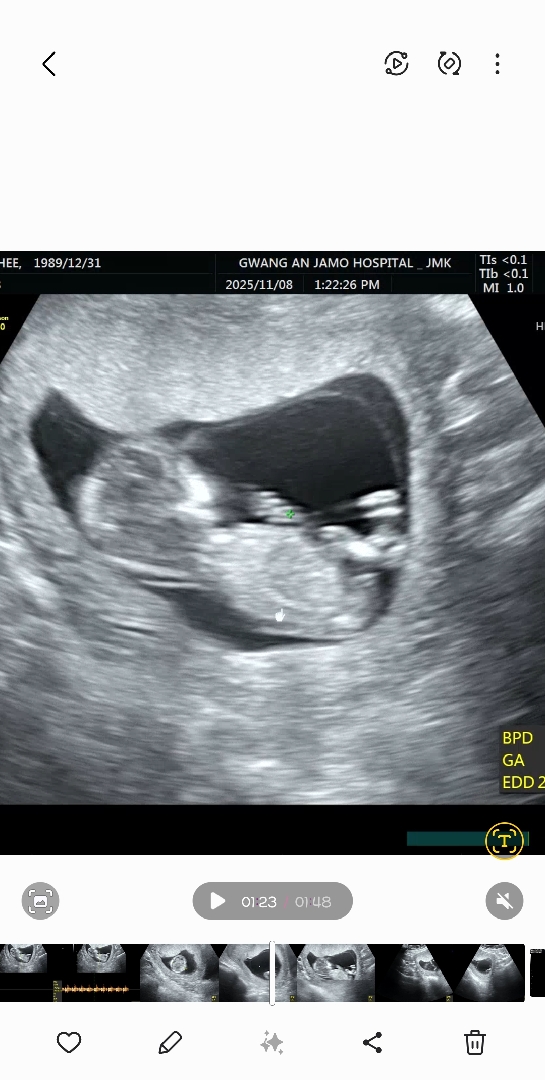

첫째 아들맘 ㅠ 둘째 성별좀 봐주세요..ㅠㅠ

아들일까요 또ㅠ